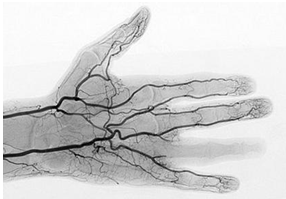

“诸脉之浮而常见者,皆络脉也。”“当数者为经,其不当数者为络也。”显然,经络是皮肉之间肉眼可见的管道,大而数目少的叫经脉(即现代医学的大动脉和静脉),小而数目多得无法数的叫络脉(小的浅表静脉网和毛细血管)。

从功能看,经络里运输的是血和气。古人言之凿凿,“脉者,血之府也”,“血之随气,循环经络”、“血循经脉”等等。中医有“血病身有痛者治其经络”(《黄帝内经》三部九侯论篇),“心者血,肺者气。血为荣,气为卫,相随上下,谓之荣卫。通行经络,营周于外”(《难经?论脏腑》),实际上就是在说经络中走的是血,有气为护。可见,经络就是血管。

人体脉络